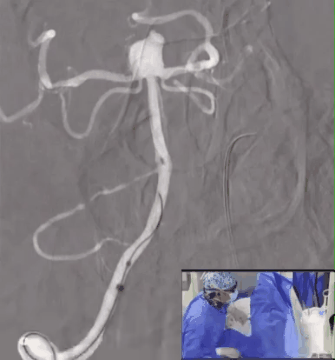

通路建立:NeuronMax 90cm超选至椎动脉起始段,6F Sofia中间导管经NeuronMax超选至V1段,VIA27微导管经Sofia超选至动脉瘤内,VIA27到位后重新路图。

释放WEB™:将WEB™ SL 9*4经VIA27缓慢推送至微导管尖端,重新做路图。

缓慢推出WEB™至萌芽状态,固定VIA,继续缓慢推出WEB™至开花状态,固定WEB™推送杆并回撤VIA完成WEB™完全释放。